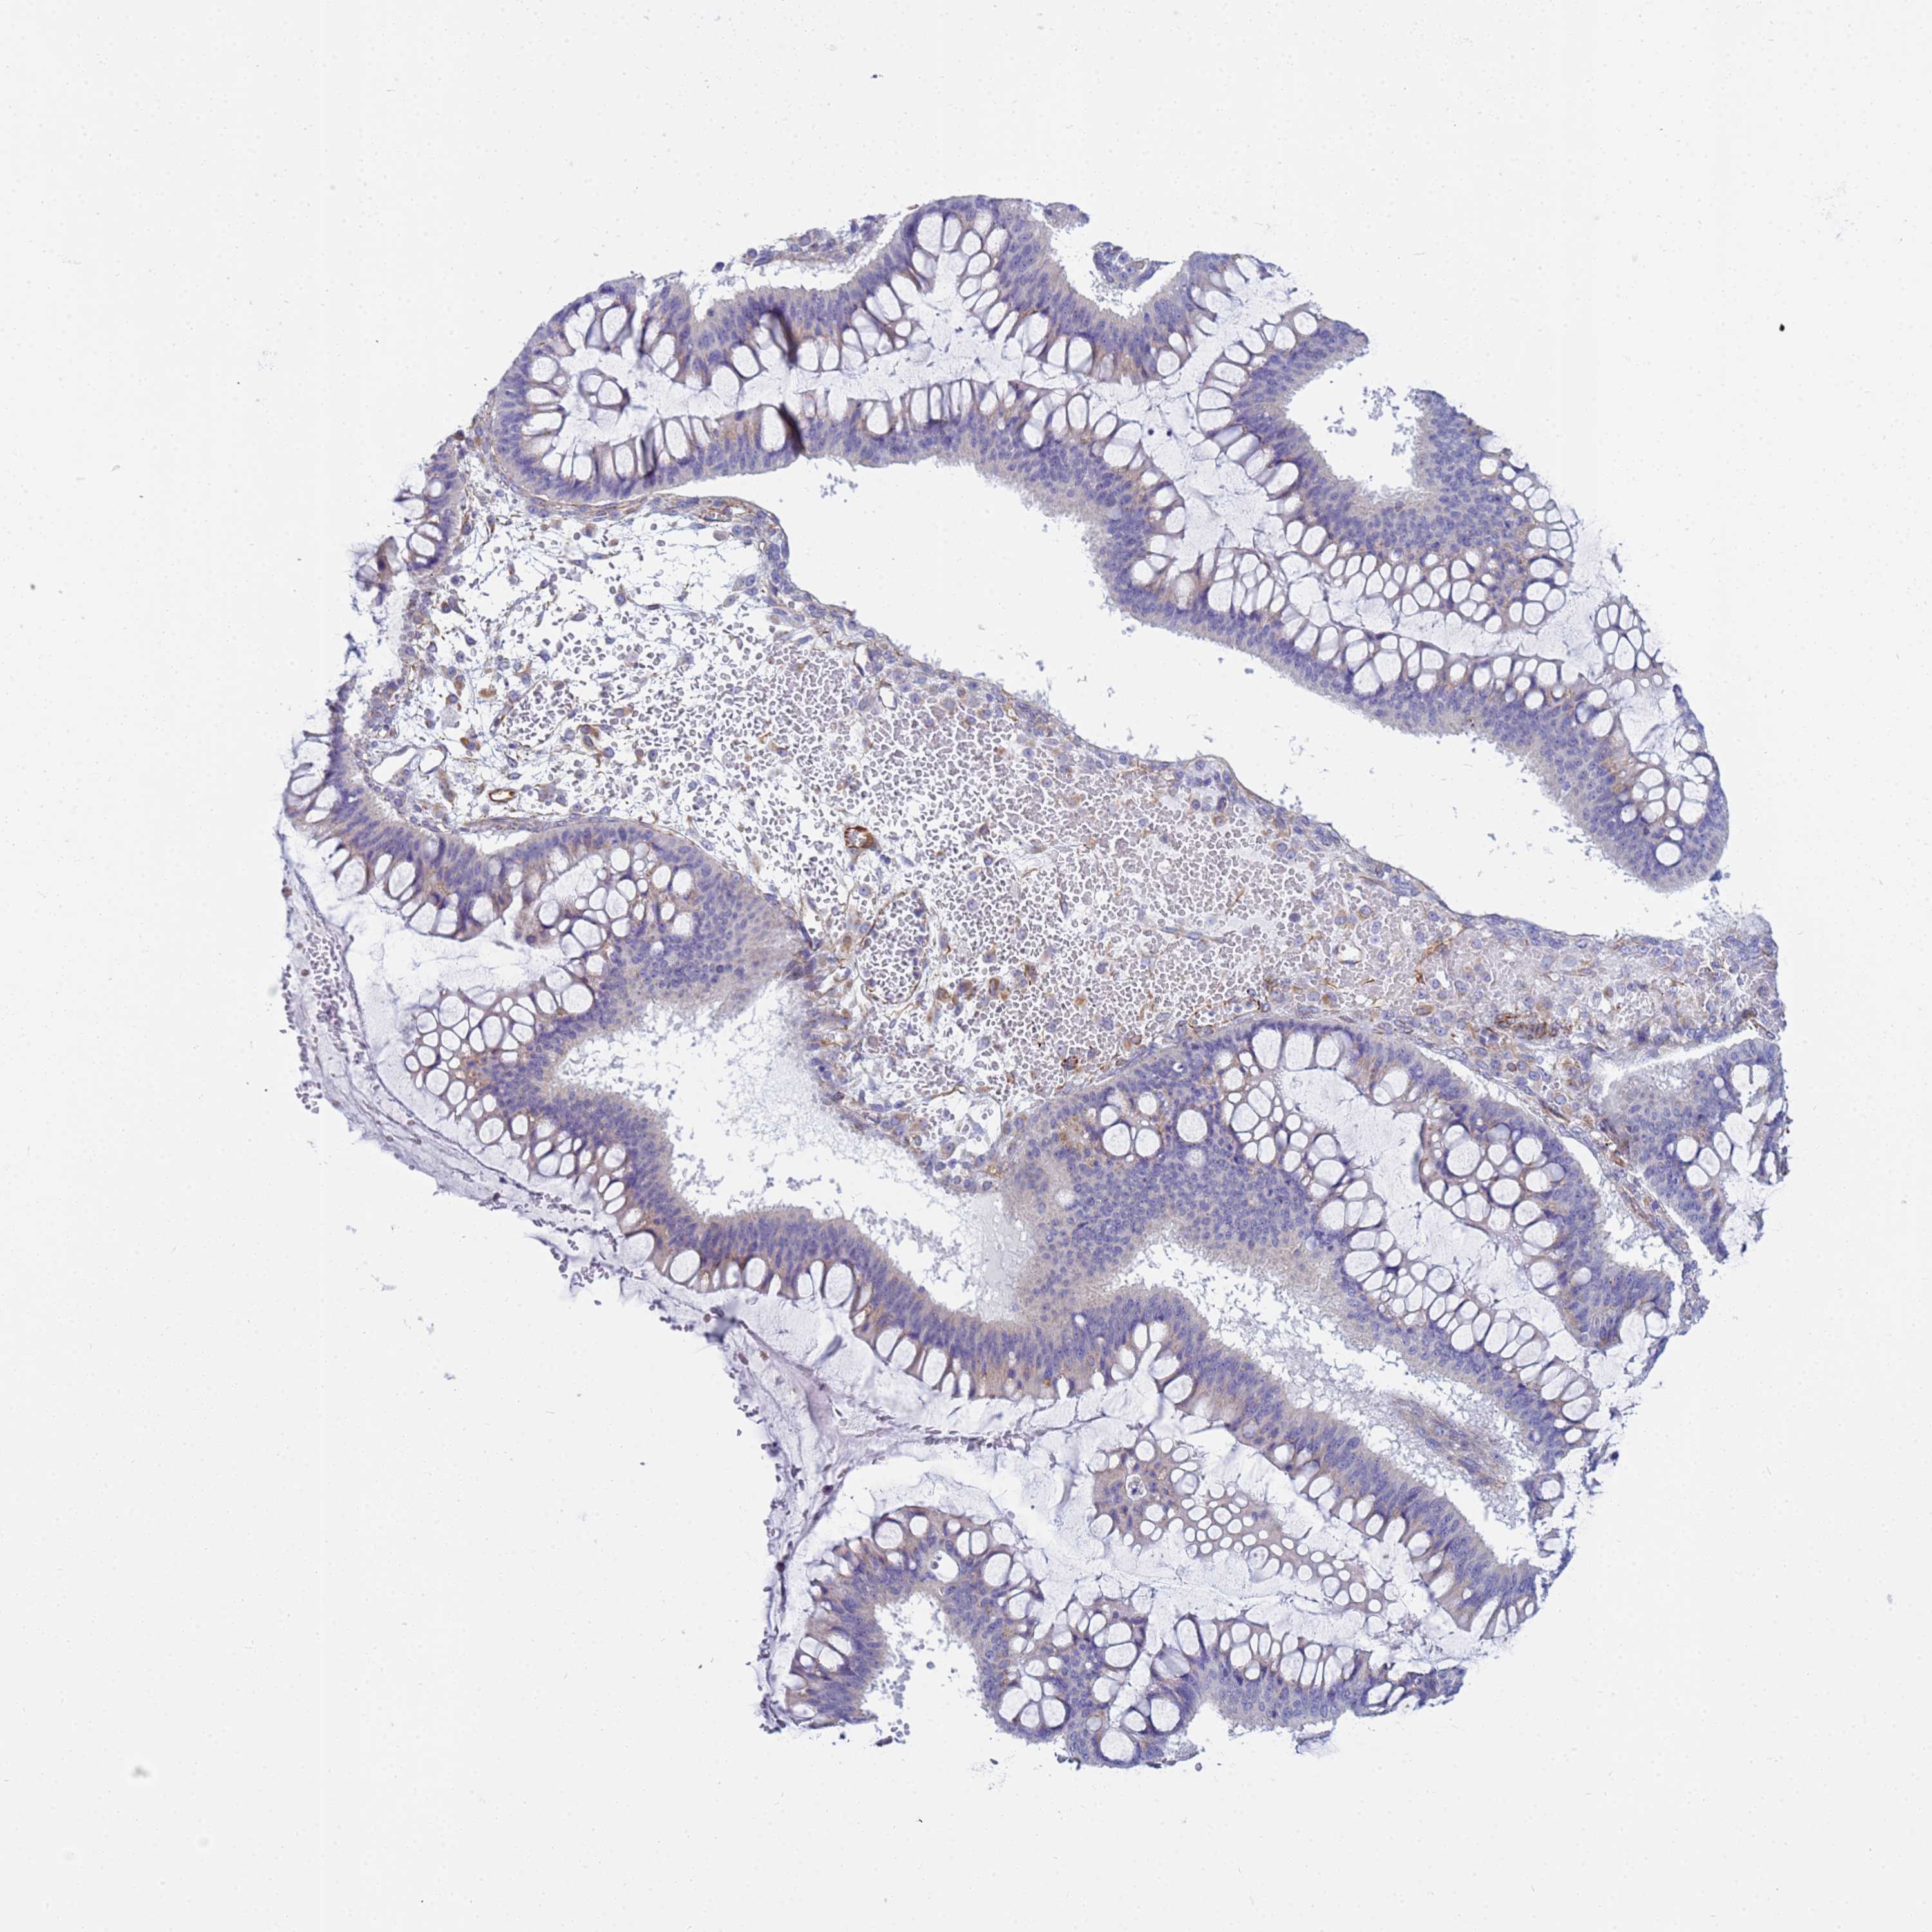

OVARIAN CANCER - Protein expressioni

A mouse-over function shows sample information and annotation data. Click on an image to view it in a full screen mode. Samples can be filtered based on level of antibody staining by selecting one or several of the following categories: high, medium, low and not detected. The assay and annotation is described here.

Note that samples used for immunohistochemistry by the Human Protein Atlas do not correspond to samples in the TCGA dataset.

Antibody stainingi

Antibody staining in the annotated cell types in the current human tissue is reported as not detected, low, medium, or high, based on conventional immunohistochemistry profiling in selected tissues. This score is based on the combination of the staining intensity and fraction of stained cells.

Each image is clickable and will lead to virtual microscopy that enables deeper exploration of all samples and also displays staining intensity scores, fraction scores and subcellular localization as well as patient and tissue information for each sample.

Antibody HPA045278

Staining

High

Medium

Low

Not detected

Intensity

Strong

Moderate

Weak

Negative

Quantity

>75%

75%-25%

<25%

None

Location

Nuclear

Cytoplasmic/membranous

Cytoplasmic/membranous,nuclear

Cystadenocarcinoma, serous, NOS

Carcinoma, endometroid

Cystadenocarcinoma, mucinous, NOS

Carcinoma, NOS